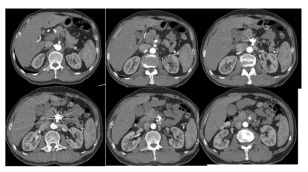

经过手术,老徐转危为安,他的腹痛明显缓解,也开始正常进食。术后一周,他的CT血管造影显示:支架通畅,假腔无显影,无并发症。老徐终于笑着出院了。

术后一周CTA